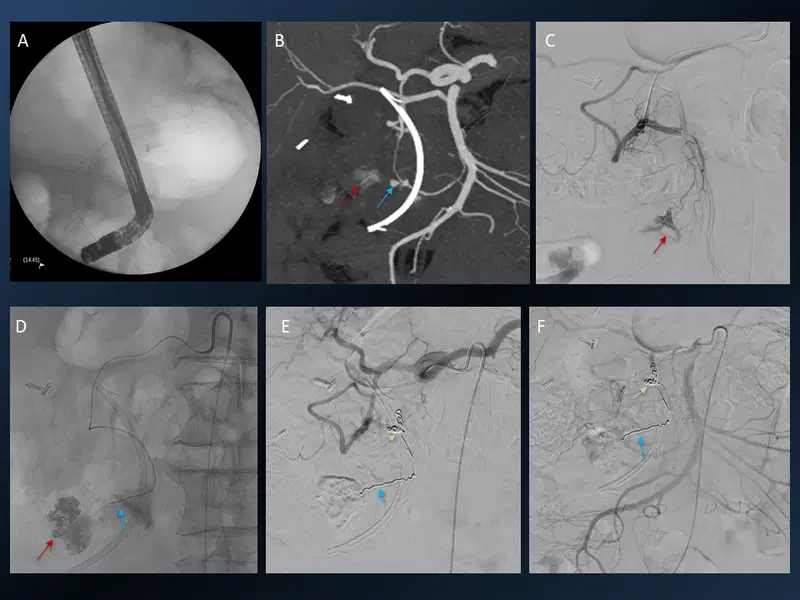

3. Mechanical Thrombectomy with aspiration only technique

Mechanical Thrombectomy with aspiration only technique CT, CT perfusion and angiogram images

Young patient with left sided dense hemiplegia while working out in gym. Time of onset 3 hrs. Plain CT demonstrates early changes of acute stroke in the right MCA territory (A). CTA confirms right M1 occlusion (B). Perfusion imaging (C) shows mismatch ratio of 7.9 with good volume of salvageable brain (green shade). DSA re-demonstrated the right M1 occlusion which was successfully removed using only suction, ADAPT resulting in TICI 3 outcome (E).